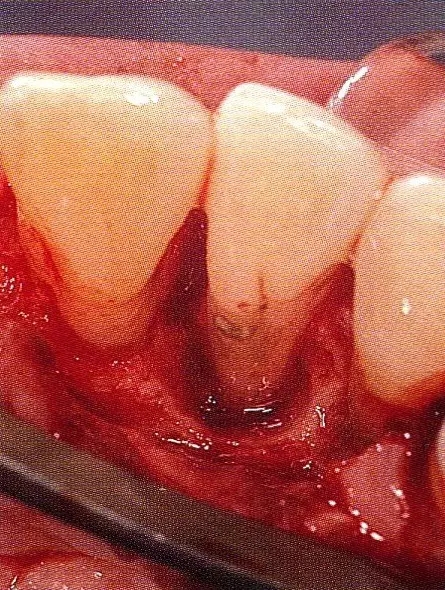

640.webp (3).jpg

▲圖7-4  術(shù)后1年2個月再翻開看的情況。與圖7-1的骨缺損狀態(tài)相比可知形成了臨床性骨再生。